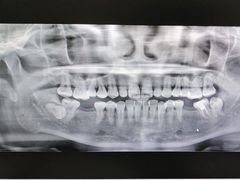

• 土豆口腔(凤凰北总店)

• -土豆口腔(凤凰北总店)